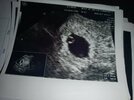

na początku ciąża jest chroniona czyli albo wszystko albo nic. Przecież nie mogłaś wcześniej wiedzieć o ciąży jak się o niej dowiedziałaś, prawda? Zaraz dodam Ci mój pęcherzyk w 5tDziekuje za pocieszenie...Martwi mnie to ze bralam ten antybiotyk i pobolewa mnie podbrzusze

to był 4 i 10. Majawidze,widze, na tym pierwszym to jakas malenka kropeczka<3